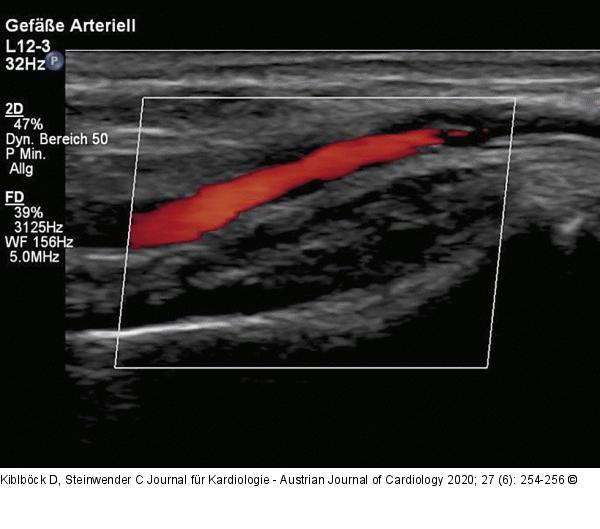

Abbildung 3: Duplexsonographie Duplexsonographischer Befund mit regelrechtem, pulsatilem Fluss der Arteria radialis ohne Stenosierung oder Verschluss nach der Biopsie. |

Duplexsonographischer Befund mit regelrechtem, pulsatilem Fluss der Arteria radialis ohne Stenosierung oder Verschluss nach der Biopsie. |